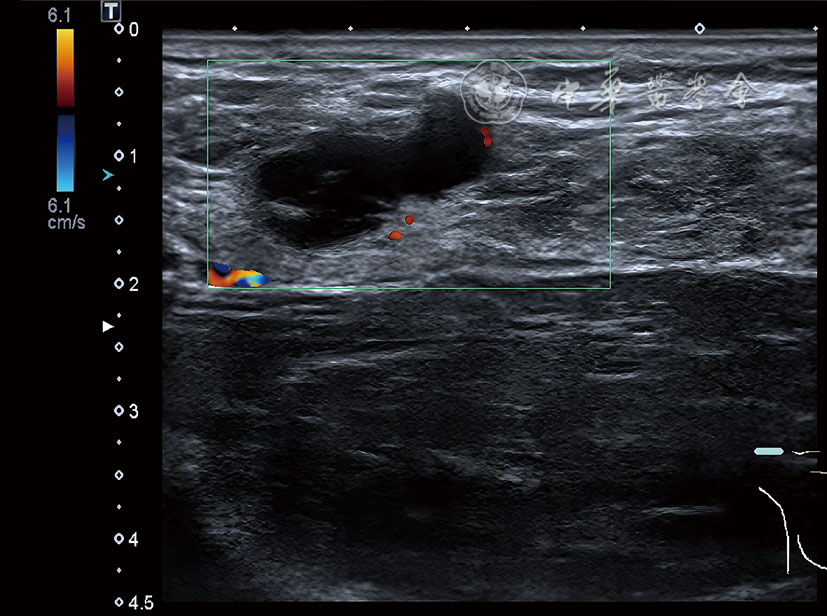

图1 男性隐匿性乳腺癌患者术前右侧腋窝超声图 注:线条勾画区示不均质低回声包块,形态不规则,边界模糊

图2 男性隐匿性乳腺癌患者术前乳腺超声图 注:绿色方框示右侧腋窝低回声结节,考虑转移性淋巴结